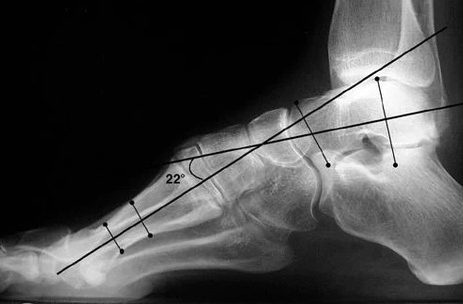

Subtle Cavovarus: A Common and Underserved Foot Deformity For over thirty years, the orthotic and footbed industry has focused on the correction of flatfoot / pronation deformities. This has led to an extensive industry of arch support products sharing many of the same features and elements in common In the meantime, there is a notable lack in both the understanding and pre-surgical treatment of the high arch or cavovarus foot alignment and especially the subtle cavovarus foot and its symptoms.' Like flatfoot, high arches are a common deformity leading to significant, under-treated symptoms. The cavovarus foot typically overloads or puts too much pressure...

Supination is what happens when your ankle doesn't roll inward enough during walking or running which causes most of the weight to be carried on the outside of the foot. This causes your foot to incorrectly displace the weight of your foot and effectively causes a continual "roll" of your ankle increasing the risk of an Ankle Sprain or torn tendons. High Arches and Cavus are other common terms for Supination. WHAT CAUSES HIGH ARCHES / SUPINATION? Heredity Misalignment of the foot bones HOW DO I KNOW IF I HAVE HIGH ARCHES / SUPINATION? WHAT ARE THE SYMPTOMS OF HIGH ARCHES / SUPINATION? Foot, hip, ankle...